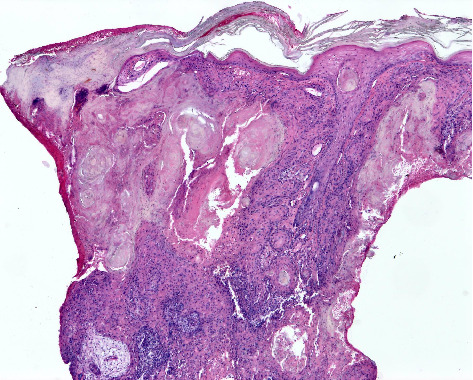

背景:皮肤鳞状细胞癌(CSCC)是全球第二常见的皮肤癌。然而,在澳大利亚和美国等国家,其发病率相对于基底细胞癌(BCC)正在上升。在南非,人口暴露于许多CSCC风险因素,包括高紫外线辐射水平和免疫抑制的高负担,在这方面描述该疾病特征的科学文献仍然明显缺乏。目的:描述南非队列中CSCC的临床、组织病理学和风险特征,以确定可以为当地临床实践提供信息的模式,并指导未来的研究重点。方法:对2019年9月1日至2020年8月31日在Tygerberg学术医院就诊的患者进行回顾性数据分析。从医疗记录中提取人口统计学和临床数据。两名研究评估人员使用预先确定的标准来审查皮肤活检的组织病理学特征。病变的风险分层遵循国家综合癌症网络的指导方针。结果:在一年多的时间里,83例患者诊断出113例CSCCs。参与者主要为Fitzpatrick皮肤光型I(65.1%)和男性(60.2%),中位年龄为73岁,男女比例为1.51:1。bcc与cscc的发病率比为1.71:1。大多数病变存在超过6个月(87.6%),位于头颈部(59.3%)。穿刺活检诊断出62.8%的病变。组织学上63.7%为高分化,40.7%为浸润性。常规CSCCs占病变的75.2%;5.3%为棘溶性高危亚型。77.0%的病变有高复发风险。结论:本研究突出了南非CSCC的异质性,强调了前瞻性、具体情况研究的必要性,以加强全国范围内的预防、早期发现和管理工作。

Background: Cutaneous squamous cell carcinoma (CSCC) is the second most prevalent form of skin cancer globally. However, its incidence is rising relative to basal cell carcinoma (BCC) in countries such as Australia and the United States. In South Africa, where the population is exposed to numerous CSCC risk factors, including high ultraviolet radiation levels and a high burden of immunosuppression, there remains a notable paucity of scientific literature characterising the disease within this context. Aims: To describe the clinical, histopathological and risk profile characteristics of CSCC in a South African cohort to identify patterns that can inform local clinical practice and guide future research priorities. Methods: A retrospective data analysis of patients seen at Tygerberg Academic Hospital between 1 September 2019 and 31 August 2020 was conducted. Demographic and clinical data were extracted from medical records. Two study evaluators used predetermined criteria to review the histopathological features in skin biopsies. Risk stratification of lesions followed the guidelines of the National Comprehensive Cancer Network. Results: Over one year, 113 CSCCs were diagnosed in 83 patients. Participants were primarily Fitzpatrick skin phototype I (65.1%) and male (60.2%), with a median age of 73 years and a male-to-female ratio of 1.51:1. The BCC-to-CSCC incidence ratio was 1.71:1. Most lesions had been present for over 6 months (87.6%) and were located on the head and neck (59.3%). Punch biopsies diagnosed 62.8% of lesions. Histologically, 63.7% were well differentiated, and 40.7% were invasive. Conventional CSCCs comprised 75.2% of lesions; 5.3% were the high-risk acantholytic subtype. A high recurrence risk was found in 77.0% of lesions. Conclusion: This study highlights the heterogeneous nature of CSCC in South Africa and underscores the need for prospective, context-specific research to enhance prevention, early detection and management efforts nationwide.